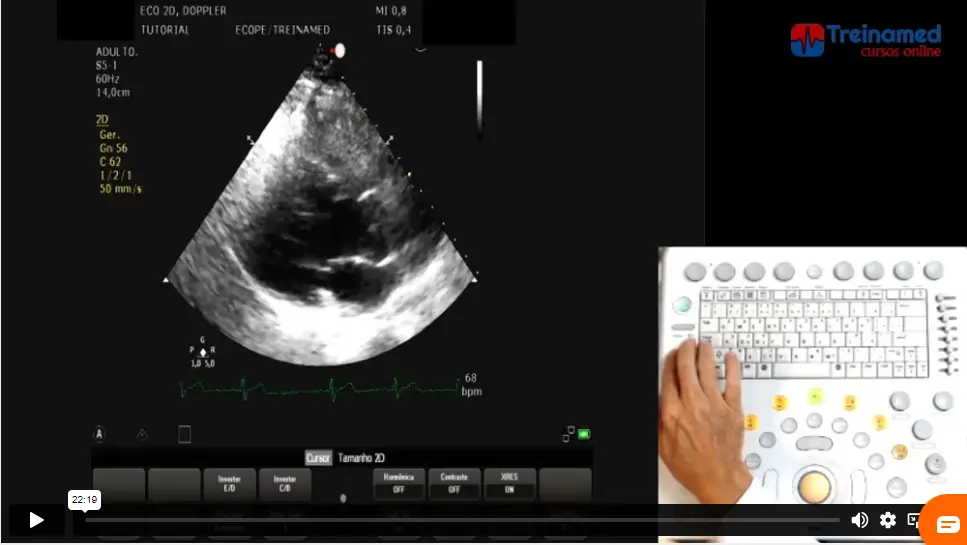

4 – Tutorial em equipamentos (PDF);